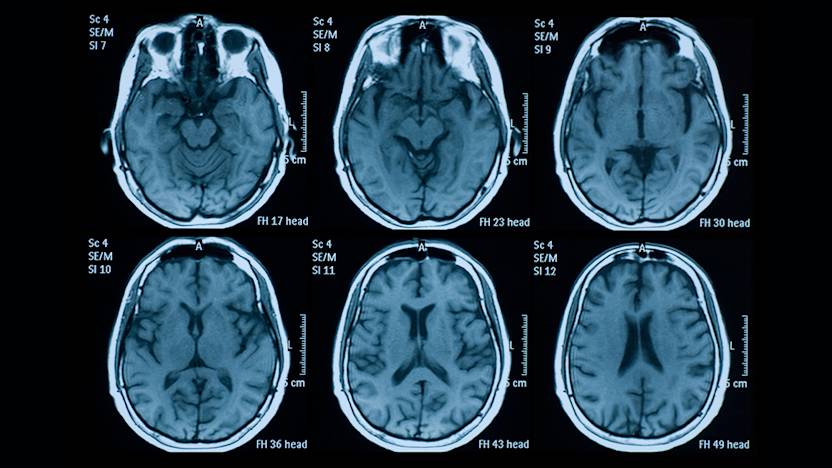

Axial T2 A And Coronal T2 B Images Of A Msa P Patient Depict Download Scientific Diagram